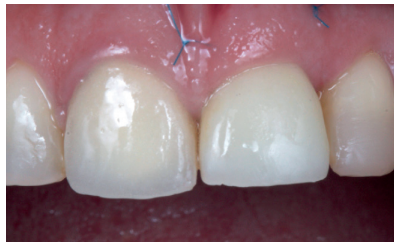

This describes the clinical case of a 52-year-old woman who came to the dentist surgery due to de-cementation of a tooth-supported metal-ceramic crown on tooth 2.1 (ICSI), see Figures 1-3. The patient reported it as of high concern for her aesthetically.

Using a 3Shape™ scanner, an intraoral pre-scan was performed, first with the tooth-supported crown in place, to obtain the anatomy of the central incisor, and then without it; thus scanning the emergence profile of the root rest; the laboratory was informed of the modification of the critical profile, thus correcting the existing recession with respect to 1.1 (Figures 5-7). This scan served in turn to take the colour of the future provisional structure7, 8. The STL file was sent to the laboratory to make the Marylandtype provisional prosthesis, in polymethyl methacrylate (PMMA), with two supports on the incisor edges of the adjacent teeth to ensure their correct positioning. According to the plan performed beforehand, this would serve as a provisional tooth, as well as surgical guide for the insertion of the OII in the ideal prosthetic position; thus avoiding possible future problems at the prosthetic level or in the integrity of the soft and hard tissues of the vestibular region (Figures 8 and 9).